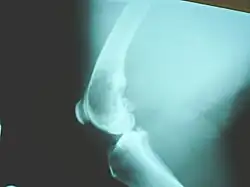

Osteosarcomas tend to occur at the sites of bone growth, presumably because proliferation makes osteoblastic cells in this region prone to acquire mutations that could lead to transformation of cells (the RB gene and p53 gene are commonly involved). The tumor may be localized at the end of the long bone (commonly in the metaphysis). Most often it affects the proximal end of tibia or humerus, or distal end of femur. Osteosarcoma tends to affect regions around the knee in 60% of cases, 15% around the hip, 10% at the shoulder, and 8% in the jaw. The tumor is solid, hard, irregular ("fir-tree," "moth-eaten", or "sun-burst" appearance on X-ray examination) due to the tumor spicules of calcified bone radiating at right angles. These right angles form what is known as a Codman triangle, which is characteristic but not diagnostic of osteosarcoma. Surrounding tissues are infiltrated.

X-rays is the initial imaging of choice to diagnose osteosarcoma. Some characteristics of osteosarcoma on X-rays are sunburst appearance and Codman triangle (elevation of bony cortex by the tumour that caused new bone formation). CT scan is helpful in defining the bony anatomy, the integrity of the bony cortex, detecting pathologic fracture, and assessing ossification (laying of new bone materials) and calcification of the cartilage. On the other hand, soft tissue and medullary cavity is better imaged by MRI scan.[23]